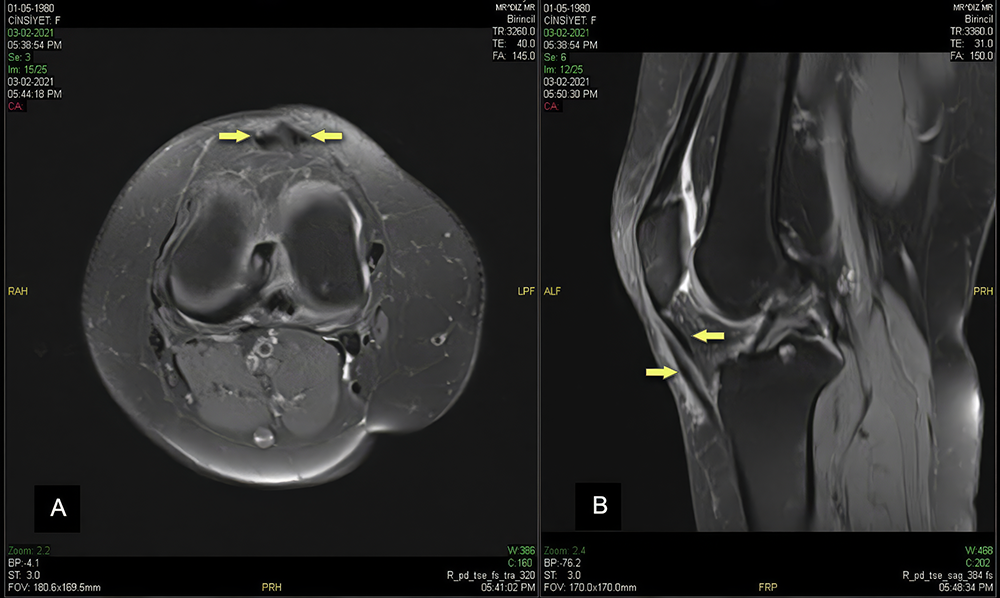

The right knee demonstrated an identical cross-double patellar tendon morphology, confirming the bilateral nature of this anatomical variant (Figure 2A, 2B).

The crossing pattern, signal characteristics, and intervening fat planes were virtually identical to those observed in the left knee, strongly supporting a congenital rather than acquired etiology. Associated findings included similar meniscal degenerative changes, full-thickness chondral thinning at the patellar apex, joint effusion with synovial proliferation, and Hoffa’s fat pad edema comparable to the contralateral knee.

Figure 2. Coronal PD (A) and sagittal T1-weighted (B) images of the right knee demonstrate cross-double patellar tendons